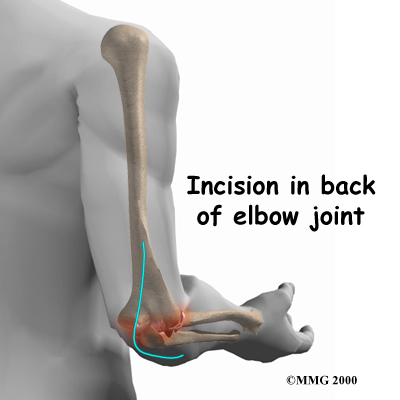

After the anesthesia, the surgeon makes an in the back of the elbow joint. The incision is made on the back side because most of the blood vessels and nerves are on the inside of the elbow. Entering from the back side helps prevent damage to them.